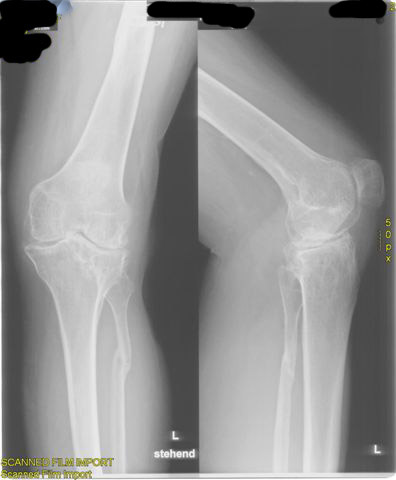

schwere Kniegelenksarthrose, Gelenksspalt innen komplett aufgebraucht

schwere X-Bein-Fehlstellung und Instabilität bei massiver Kniegelenksarthrose